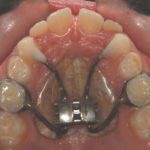

L’espansione del palato, come e quando attuarla

Rappresenta senza dubbio il “gold standard” nei casi di morso crociato in pazienti in crescita, tuttavia è possibile effettuare tale terapia anche in altre circostanze. Lo spiega Alberto Caprioglio, direttore della Scuola di specializzazione in Ortognatodonzia presso l’Università degli Studi dell’Insubria, rispondendo ai dubbi di una giovane odontoiatra.